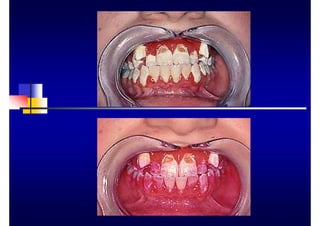

• Encía fibrótica, con engrosamiento de los

márgenes

• Mínimo enrojecimiento gingival en relación con

la gravedad de la enfermedad

• Mayor gravedad y progresión en relación con

los no fumadores de la misma edad

• Recesión gingival en segmentos anteriores

• No existe relación entre el estado periodontal y

el nivel de placa y cálculo

• Inicio de la enfermedad relativamente temprano,

entre los 20 y los 30 años

• Progresión rápida de la enfermedad

• Reaparición de bolsas después de un año del

tratamiento

• Resistencia al tratamiento convencional